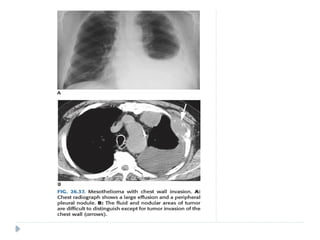

MALIGNANT MESOTHELIOMA

⚫ Highly malignant and locally aggressive tumor

⚫ 6th or 7th decade of life

⚫ Associated with asbestos exposure, with an average latency of

35-40 years for its development.

⚫ Other predisposing factors :

⚫ Radiation therapy

⚫ Tuberculosis

⚫ Chronic empyema

On imaging :

⚫ Diffuse nodular pleural thickening – pleura along the

intercostal spaces, costophrenic angles and lung apices

are involved.

⚫ Pleural plaques (latent period of formation is 20yrs; strong

indicator of asbestos exposure): usually seen adjacent to ribs.

Involving sixth to ninth rib. These themselves are not

premalignant

⚫ Pleural effusion

⚫ Calcifications may be seen along diaphragmatic pleura.